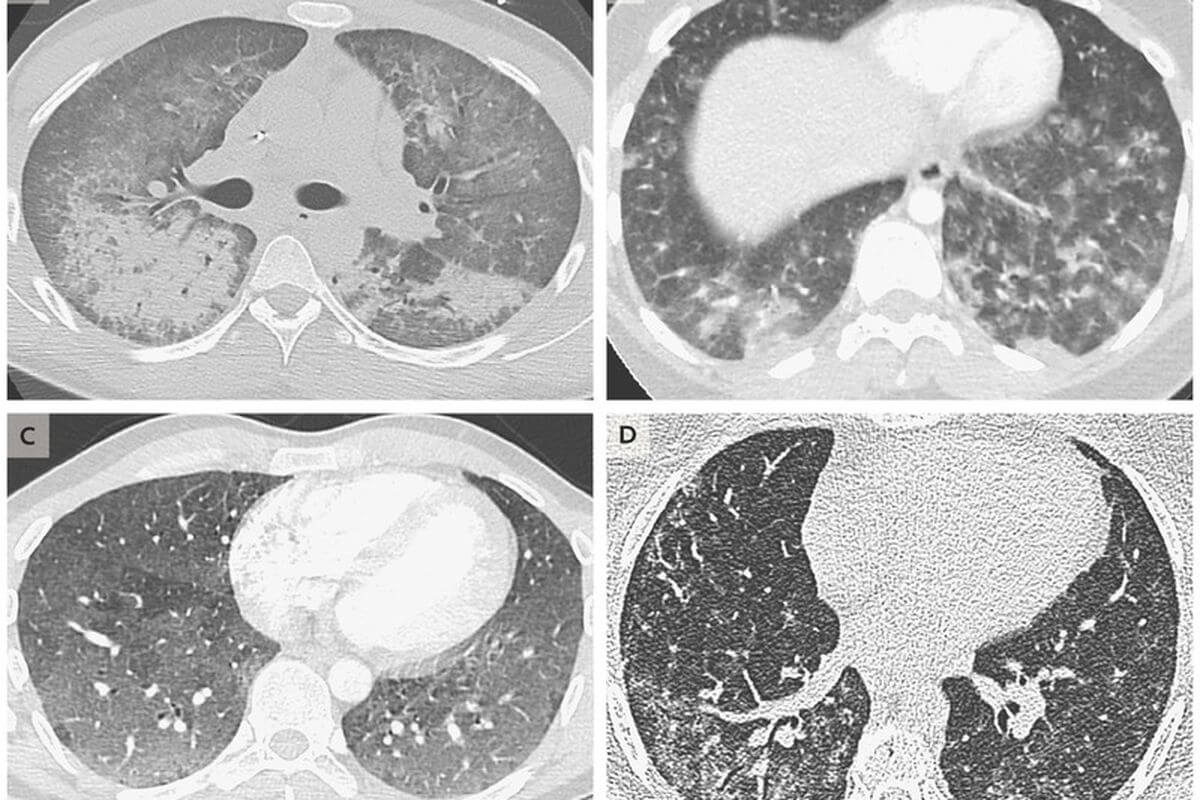

Вот так выглядят поврежденные ткани легких пациентов